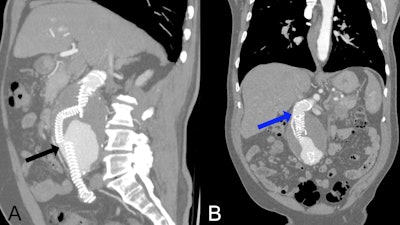

Postoperative CT angiography at presentation shows type Ia and type IIIa endoleaks. (A) Multiplanar reconstruction in a predominantly sagittal plane with maximum intensity projection (MIP) showing a type IIIA endoleak (black arrow) caused by disconnection between the limb extension and the branch of the Anaconda bifurcated endograft. (B) Multiplanar reconstruction in a mainly coronal plane with MIP demonstrating a type 1A endoleak (blue arrow) originating from the proximal seal zone and extending into the aneurysmal sac.Dr. Juan Carlos Gomez-Rodriguez et al and Cureus